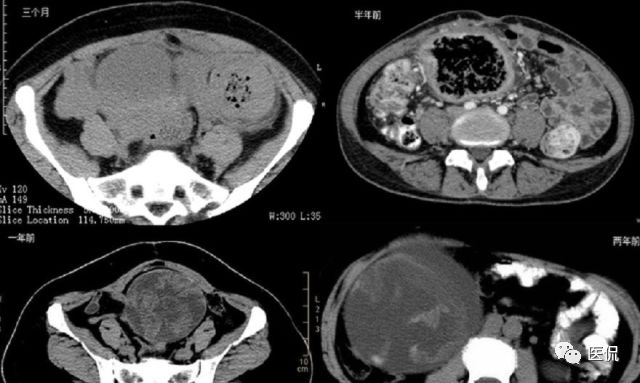

女 40岁 ,10年前做个剖腹产术。之后到现在一直感觉肚子疼,去很多医院做检查 诊断肠结核,经过反复抗结核治疗。病人10年瘦了几十斤。

腹腔内残留的纱布在人体内引起渗出或液化坏死并纤维包裹形成异物性脓肿(纱布瘤)。纱布瘤的影像特点:圆形或卵圆形肿块,较大,有完整包膜,薄壁,较少的情况下为厚壁,边界较完整,增强后薄膜可以持续强化。不同时期的纱布瘤可以有不同表现:早期(10个月或半年内)多表现为蜂窝状;2~5年内一般表现为囊性飘带状;10~20年之后则为实性软组织密度,包膜钙化呈钙化网状结构。手术过程中残留在人体内的医用纱布所形成的肿瘤样病变。